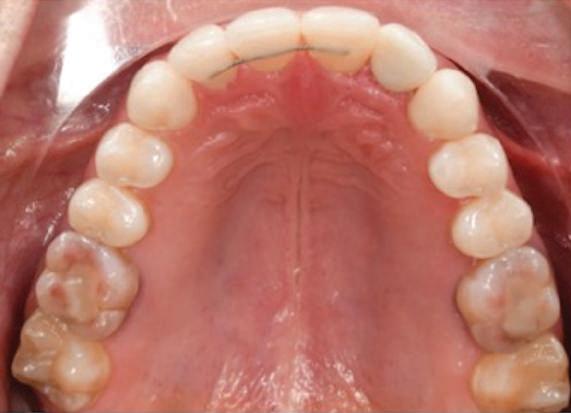

Dental Tribune Bulgarian Edition / октомври 2022 г.16 клиничен случай с алайнери Г орният латерален ре зец е вторият найчесто вродено липсващ зъб.1,2 Поради разполо жението му във видимата зона на усмивката лечение то на подобни случаи нала га мултидисциплинарен под ход, целящ отличен функцио нален и естетичен резултат. Налице са няколко лечебни мо далности, свързани с различ но разпределение на място то: първият вариант е орто донтско отваряне на място и възстановяване на липсва щия зъб с конструкция, под държана от съседните зъби3 или от имплант4, докато при втория подход разстоянията се затварят и премоларът заема мястото на канина.5 Изборът на лечебен подход трябва да бъде направен съв местно от зъболекар и паци ент въз основа на очакванията на последния и предвиди мостта на лечението. Множе ство фактори влияят върху това решение, като напри мер типа малоклузия, размера, формата и цвета на кучеш ките зъби6, оклузалните вза имоотношения (овърджет и овърбайт), лицевия профил, дължината на зъбната дъга и несъответствията в разме ра на зъбите.7 В настоящата публикация се разглежда случаят на жена в зряла възраст с вродена лип са на горен ляв латерален резец. Бяха приложени про зрачни алайнери за отваряне на място за единичен им плант и бяха постигна ти функционална оклузия и отлична естетика. ПРЕДСТАВЯНЕ НА СЛУЧАЯ Диагноза Пациентката бе на 32 годи ни, когато лечението започна, и първоначалното ѝ състоя ние бе следното (фиг. 1–3): липсващ горен ляв латерален резец; клас II, подклас I малоклузия; отклонение на горната сре динна линия вляво; Доклад на клиничен случай ЛЕЧЕНИЕ С АЛАЙНЕРИ НА ПАЦИЕНТ С АГЕНЕЗИЯ НА ЛАТЕРАЛЕН РЕЗЕЦ Д-р Iro Eleftheriadi и д-р Christodoulos Laspos, Гърция и Кипър Фиг. 1a–h Предоперативни лицеви и интраорални снимки. Фиг. 2a–e Дигитални модели преди началото на лечението. Фиг. 3 Панорамна снимка преди лечението. Фиг. 1a Фиг. 1d Фиг. 1f Фиг. 2a Фиг. 2d Фиг. 2b Фиг. 2e Фиг. 3 Фиг. 2c Фиг. 1b Фиг. 1e Фиг. 1g Фиг. 1h Фиг. 1c

Dental Tribune Bulgarian Edition / октомври 2022 г. 17клиничен случай с алайнери леко струпване в долната че люст; несъответствие по Болтън (мандибуларен излишък от 3.06 мм във фронталната зона и общо 1.47 мм); издължено лице с лицева аси метрия; конвексен профил с ретруди рана долна челюст и проми нентен нос. На мястото на зъб #46 бе на лице имплант, а зъби #16 и 26 са ендодонтски лекувани. Тези зъби бяха асимптоматич ни, затова бе взето решение да се прави релечение само при нужда. Мъдреците липсваха. Анализът на телерентгеногра фията (фиг. 4) показа ретрог натна мандибула (SNB: 74.2°) и нормална инклинация на резците както в

Цели на лечението и лечебен план Целите на лечението бяха следните: нивелиране и подреждане на зъбите и в двете зъбни дъги; отваряне на пространство за липсващия латерален резец; коригиране на отношенията при канините и моларите до клас I; и корекция на отклонението на срединната линия. Лечебният план включваше: корекция на отношенията при кучешките зъби и мола рите до клас I с дистализира не на максилата; отваряне на пространство в областта на #22 за поставя не на единичен имплант; корекция на срединната ли ния; и създаване на място за раз ширяване на зъб #12 и апрок симална редукция в долната челюст с цел подобряване на несъответствието по Болтън и осигуряване на подобра оклузия. Изпълнение на лечебния план Този случай бе изпълнен със системата за алайнери Invisalign (Align Technology). Одобреният първоначален лечебен план предвиждаше 49 алайне ра с дистализиране на задни те горни зъби до клас I (прибли зително с около 3.5 мм; фиг. 5). За бъдещия имплант в областта на липсващия латерал бе планирано пространство от 6.5 мм, докато във фронталния сегмент на долната челюст бе предвидена апроксимална редук ция. В дясната страна бутон за ластици клас II бе поставен на зъб #47 вместо на зъб #46, за да не се увреди короната на импланта. Понеже пациентката жи вееше в чужбина,